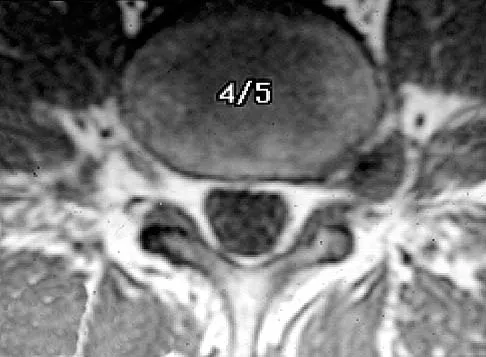

Question 17

Figures 23a and 23b show the MRI scans of a 50-year-old woman who has increasing gait disturbance. She reports three falls in the past week. Examination reveals hyperreflexia, motor weakness in the biceps and triceps, and a positive Hoffman's sign. What is the most appropriate treatment plan?

Explanation